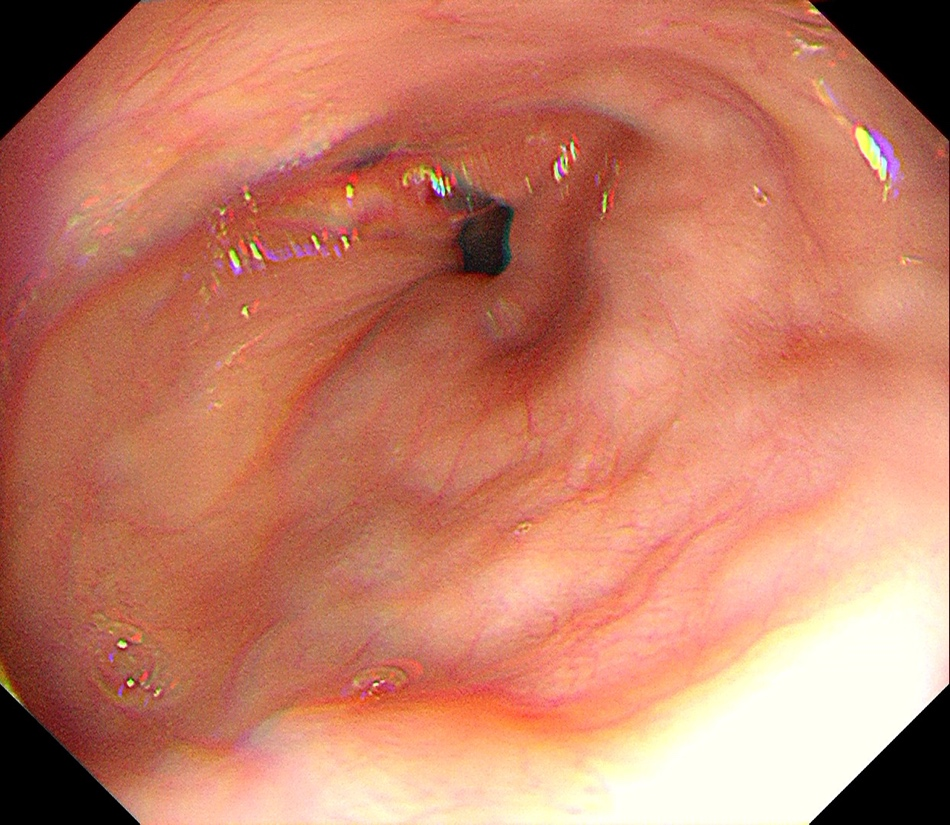

由于手术是在微创方式下完成,古先生术后并未感觉到明显的疼痛,整个人的精神也非常好,在胸科四区护理团队的呵护下,术后1天就下床走路,术后第3天,胃镜下可以看到原先的肿物已经完全消失,狭窄的食管已经恢复正常,食管粘膜完整无损。

术后胃镜检查可见肿瘤消失,食管粘膜完整无损